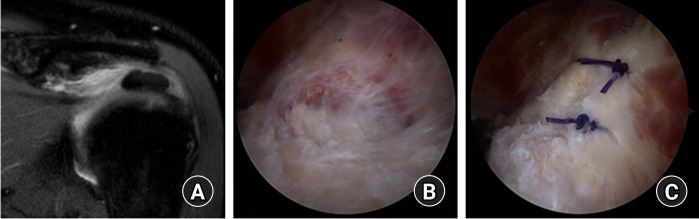

Fig. 3.

Arthroscopic decompression and rotator cuff repair using suture anchors. (A) Preoperative fat suppressed T2-weighted magnetic resonance imaging coronal view shows calcific deposits in the supraspinatus tendon insertion site. (B) Arthroscopic findings after removal and debridement of calcific deposits lesion and an approximately 2.5×1.5-cm-sized defect is seen. (C) Arthroscopic rotator cuff repair is performed using suture anchor.

그림 3.

봉합 앵커를 이용한 관절경적 감압술 및 회전근개 봉합술. (A) 수술 전 지방 억제 T2 가중 자기공명영상 관상면에서 상근 건 부착부에 석회화 침착물이 관찰됨. (B) 석회화 병변을 제거하고 정복한 후 관절경 소견에서 약 2.5×1.5cm 크기의 결손이 관찰됩니다. (C) 봉합 앵커를 이용한 관절경 회전근개 봉합술을 시행합니다.